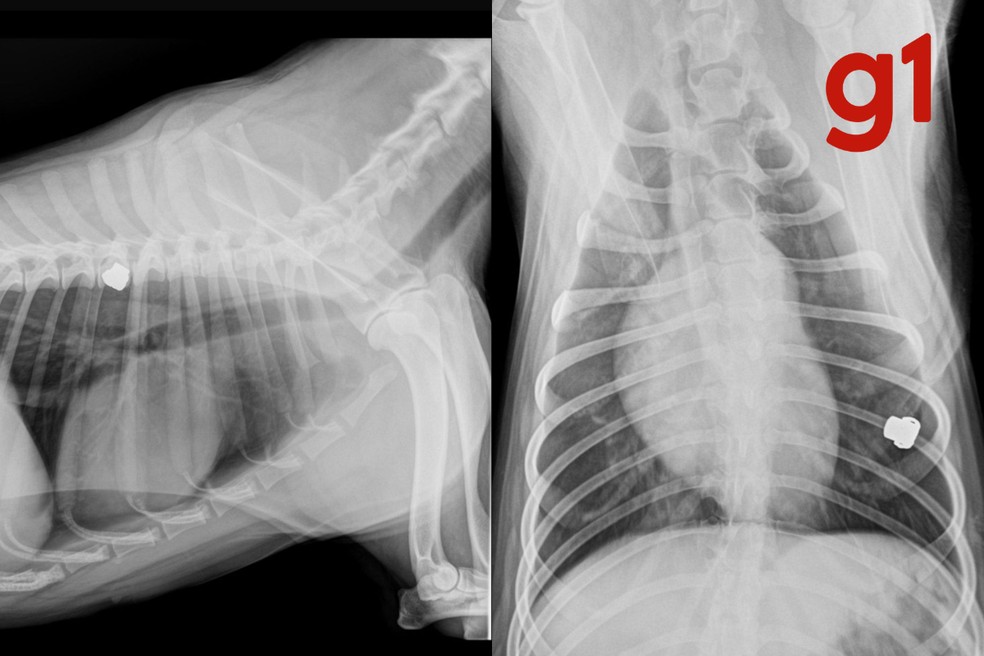

A clínica veterinária informou Claudiney de que a cachorra não corre risco de morte, no entanto perdeu a visão do olho atingido pelo tiro. Em imagens de raio-x, é possível ver que a bala ficou alojada próximo à costela do animal.